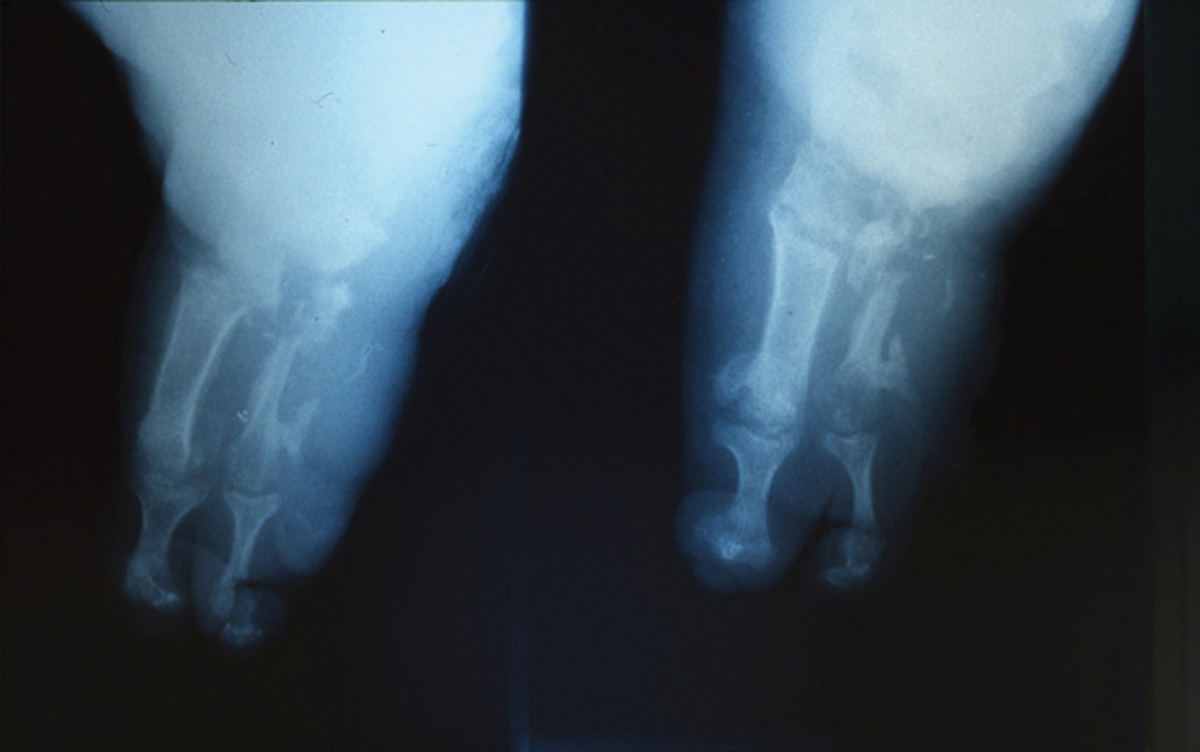

Il s’agit d’une lèpre. La lèpre est due au bacille de Hansen. Bien qu’en régression notable, elle est encore fréquente en Asie, en Amérique latine et en Afrique. Le diagnostic de lèpre est généralement évoqué devant des lésions cutanées hypochromiques et anesthésiques très caractéristiques. Cependant, il existe de nombreux autres symptômes en fonction de l’état immunitaire du sujet et du stade évolutif. Les troubles neurotrophiques sont responsables d’altérations cutanées (peau amincie, ongles déformés, maux perforants plantaires qui se surinfectent) et osseuses (ostéolyse, avec un aspect radiologique en « sucre d’orge sucé »), aboutissant à des mutilations des doigts et des orteils comme sur cette radiographie.